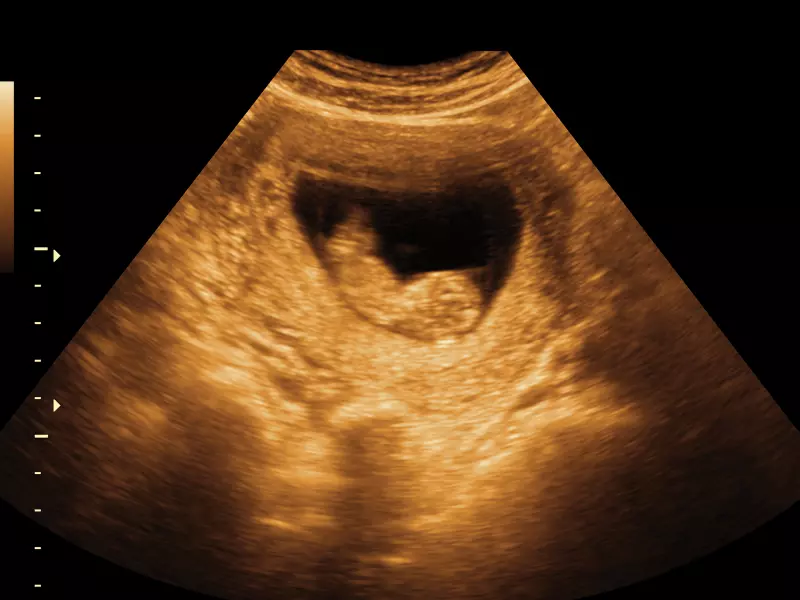

Rozszczep jest wadą rozwojową polegającą na niepołączeniu się w życiu płodowym odpowiednich wyrostków, z których powstają twarz oraz jama ustna. Rozszczepy podniebienia pierwotnego i wtórnego zaliczają się do najpoważniejszych, a zarazem najczęściej występujących wad rozwojowych twarzowej części czaszki (Ellis III 2001). Etiopatogeneza rozszczepów nie jest do końca wyjaśniona, wiadomo jednak, że na ich powstanie mają wpływ czynniki genetyczno-środowiskowe. Obecnie większość wad rozszczepowych rozpoznaje się już w okresie ciąży podczas badania ultrasonograficznego (USG).